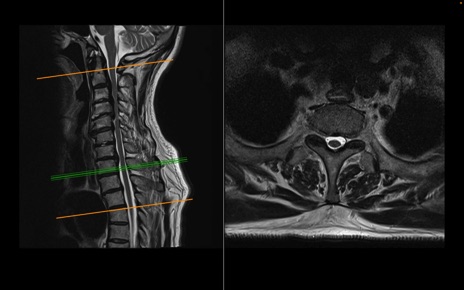

頚椎MRI

T2WI(横断像)

T2WI(矢状断像)